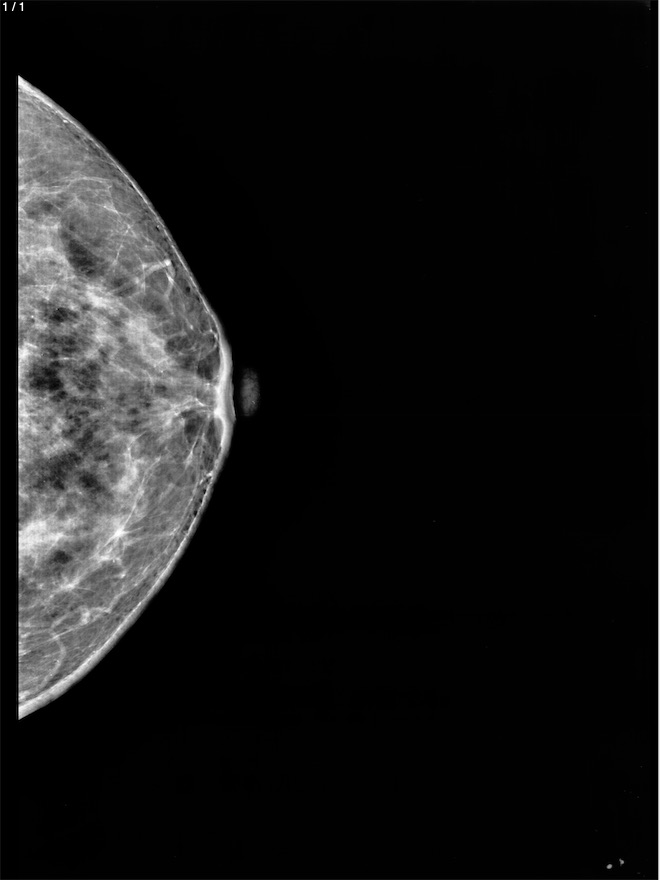

Clementina Hidalgo Cruz - Unnamed